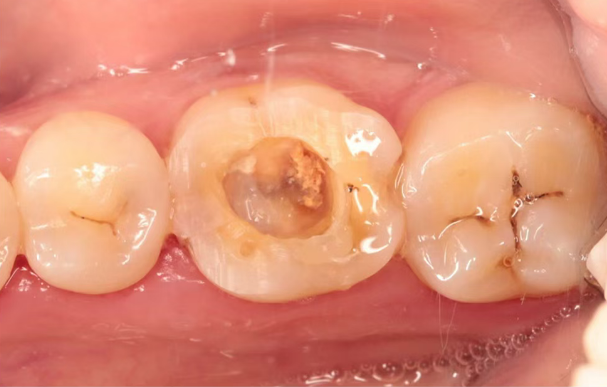

第一次就诊

涡轮机去除冠部修复体,再治疗锉去除根管内大部分充填物,

未能完全疏通,ZOE暂封

第二次就诊

上障,去封,手用C锉疏通根管全长,

机用锉扩至5004#,3%NaClO+17%EDTA冲洗液彻底化学预备,

赛特力P5活化,蒸馏水置换后干燥根管,

封入恩普诺氢氧化钙根管消毒糊剂,特氟龙+玻璃离子暂封,两周复诊。